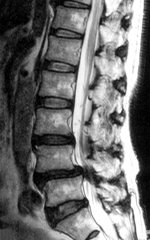

MRIによって神経の圧迫の程度がわかります。

4と第5腰椎の間で硬膜管が圧迫されている